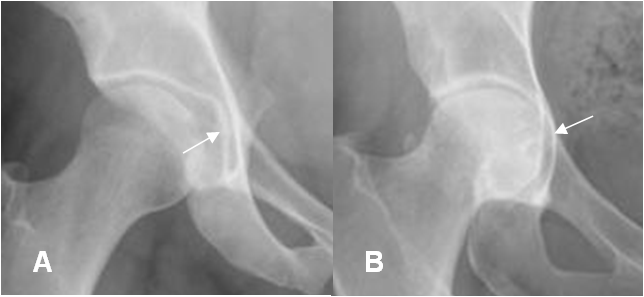

Fig 94. Coxa profunda.

A: Rx AP. Coxa normal. El techo acetabular es lateral, a la línea ilioisquial.

B: Rx AP. Coxa profunda. El techo acetabular es medial, a línea ilioisquial.